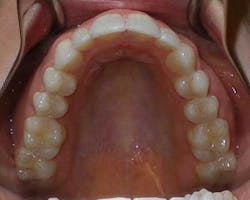

A 27-year-old female presented with a chief complaint of crowding on the upper and lower arches. Upon evaluation, it was noted that the patient had 2 mm and 4.5 mm of maxillary and mandibular arch length deficiency respectively, a missing lower left second bicuspid with primary tooth still present, small upper lateral incisors, cross-bite of the lower right canine, and lower midline shift to the right of 2 mm. (Figs. 1-8)

Figs. 1-8